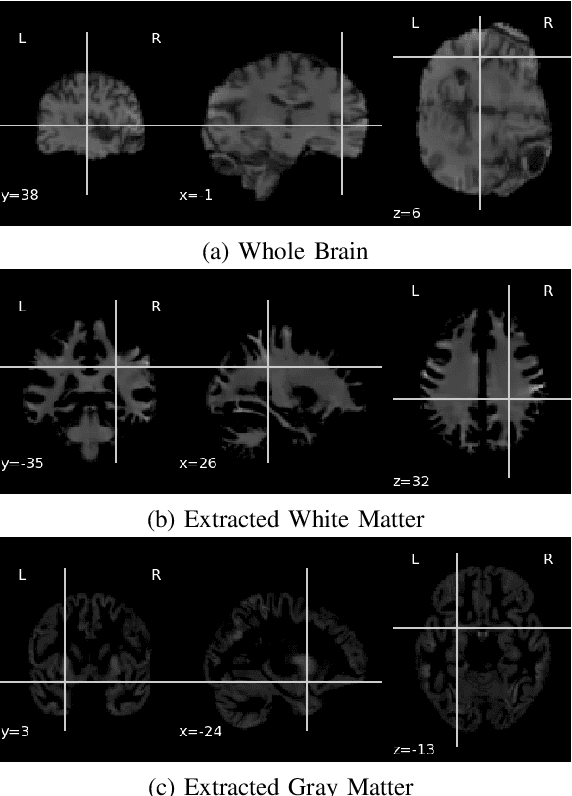

Abstract:Parkinson's Disease(PD) is one of the major nervous system disorders that affect people over 60. PD can cause cognitive impairments. In this work, we explore various approaches to identify Parkinson's using Magnetic Resonance (MR) T1 images of the brain. We experiment with ensemble architectures combining some winning Convolutional Neural Network models of ImageNet Large Scale Visual Recognition Challenge (ILSVRC) and propose two architectures. We find that detection accuracy increases drastically when we focus on the Gray Matter (GM) and White Matter (WM) regions from the MR images instead of using whole MR images. We achieved an average accuracy of 94.7\% using smoothed GM and WM extracts and one of our proposed architectures. We also perform occlusion analysis and determine which brain areas are relevant in the architecture decision making process.